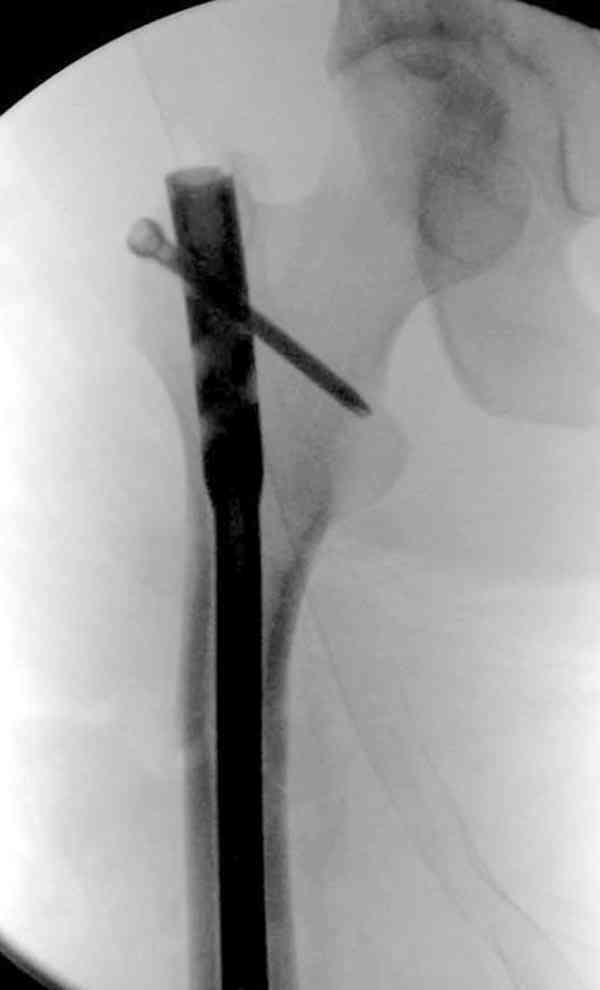

Если имеете доступ к trochanteric медуллярным штифтам TAN Smith Nephew или DePuy, где имеется offset на 8 градусов для удобства черезвертельного введения и профилактики нарушения кровеснабжения

головки (см. снимок) можно было применить штифт, в котором опороспособность достигается за счет блокирующих шурупов сверху и снизу.